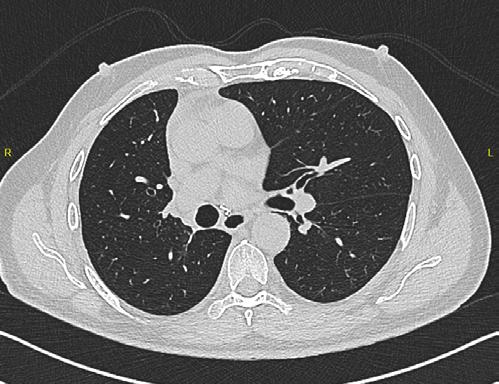

La TC de baja dosis, es la modalidad de imagen más utilizada como método de escrutinio para la detección de lesiones pulmonares, es un estudio rápido, que no requiere preparación previa. ESCANERS DE UN PACIENTE CON

Figura 1-4. Estudio de tomografía simple de tórax, con reconstrucción volumétrica, multiplanares con ventana para pulmón y en mediastino (, en donde se observa el nódulo pulmonar sólido de bordes lobulados hipodensos.

Se realiza cirugía con lobectomía inferior derecha, con resultado histopatológico de tumor carcinoide atípico, se realiza seguimiento con tomografía simple de tórax sin complicaciones en el lecho quirúrgico.

Figura 6. Estudio de seguimiento postlobotomía.